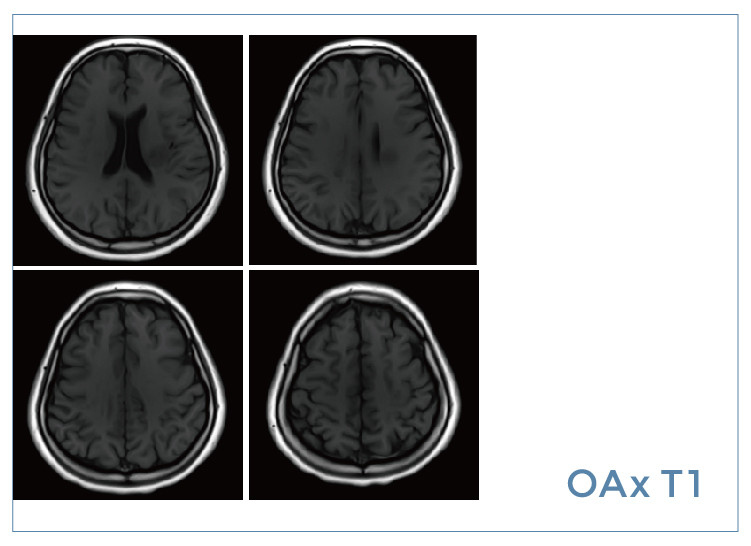

【朗润影像档案】磁共振影像病例分享(编号20190823)